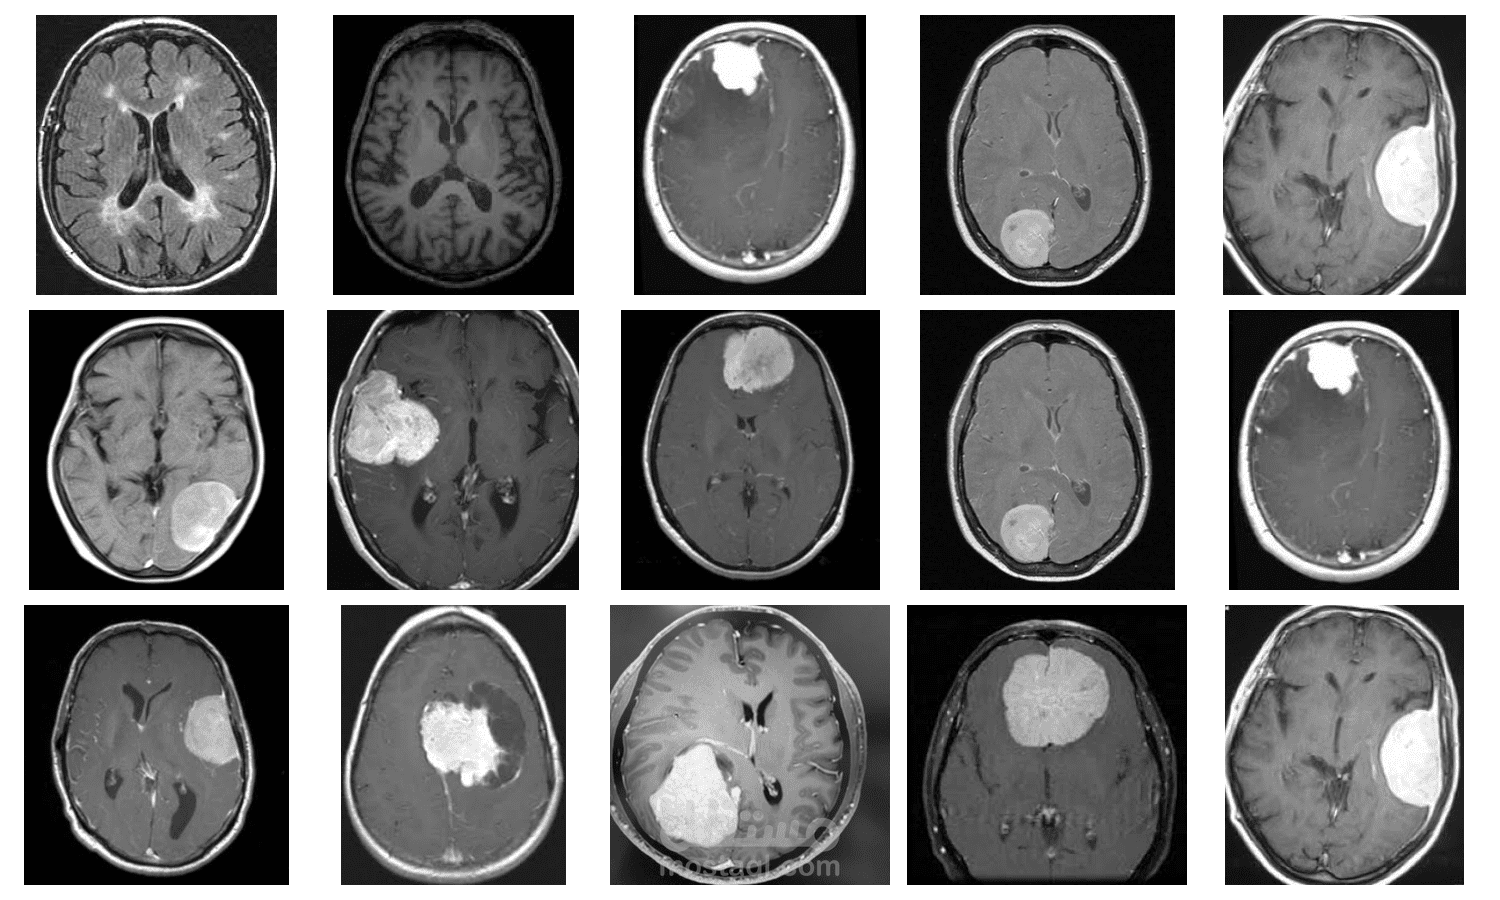

المشروع يهدف إلى تطوير نظام ذكي لتصنيف أورام الدماغ باستخدام تقنيات التعلم العميق، مع التركيز على نموذج VGG16 الذي يُعد من أبرز النماذج الفعالة في هذا المجال. يسعى المشروع إلى تمكين الأطباء والباحثين من تحليل الصور الطبية بدقة وكفاءة.

- الاعتماد على تقنيات متقدمة: استخدام نموذج VGG16 المعروف بأدائه المتميز في تحليل الصور.

- دقة عالية في التصنيف: توفير نتائج دقيقة لدعم القرارات الطبية.